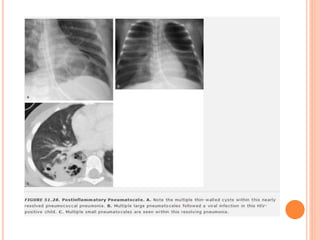

CAVIDADES: PNEUMATOCELES

 Paredes finas

 Ocorrem em infecções  PNM estafilocócica

 Decorrentes da obstrução bronquiolar  retenção

de ar e ruptura alveolar

 Podem causar efeito expansivo se se tornam

grandes

 Ruptura Pneumotórax ou pneumomediastino